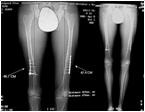

M.K.  DOB: 09.04.87

Amyoplasia

Pre Op

LLD of 3.5cm R 1.7 cm Femur 1.8 cm Tibia

Back pain

Post Op

Immediately